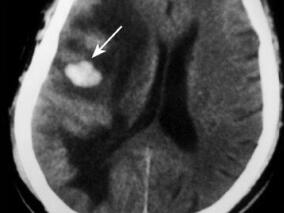

1小时条评论1 病例简介 患者男,65岁,因左侧口角流涎2个月余,左侧肢体无力12日于2008年12月5日以脑出血收入我院。 图4.7-1颅脑CT示右侧颞顶叶片状高密度出血影,周围可见指样低密度水肿影(箭头) 现病史:患者在起病前2个月(2008年9月14日)出现左侧口角歪斜、流涎,...